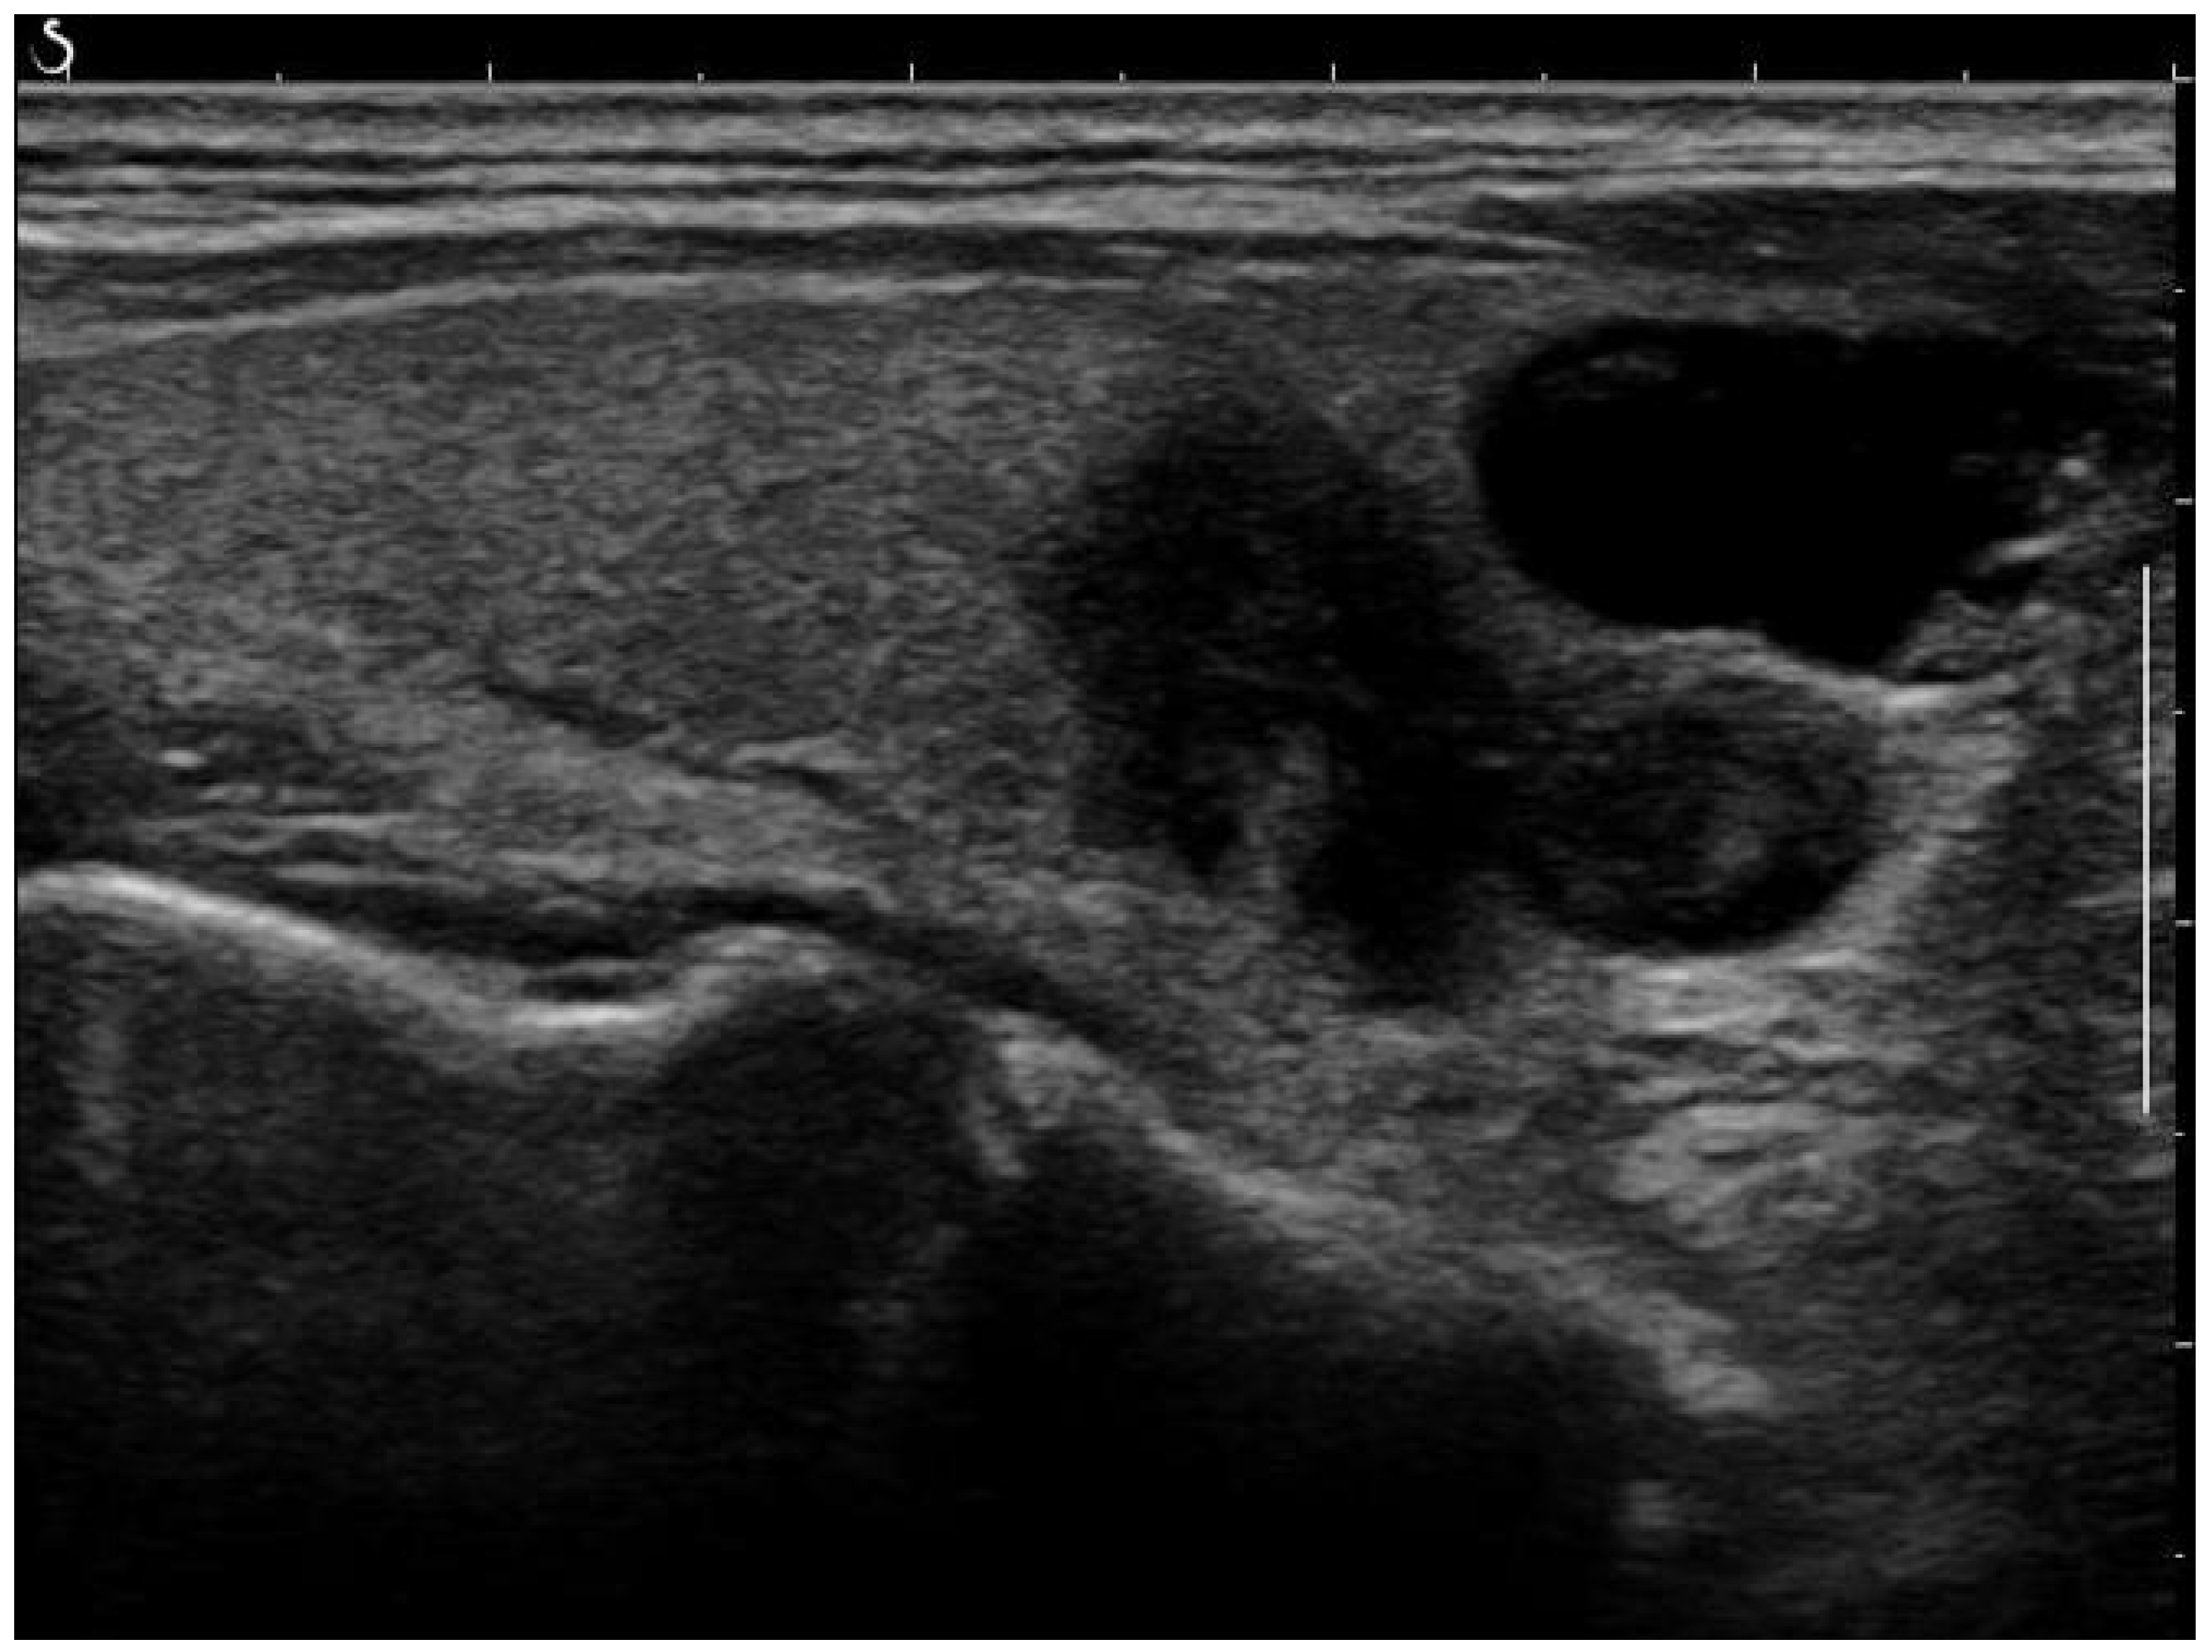

The acquisition settings varied due to differing clinical practices across the hospitals. For our study and analysis, we used retrospective data collected from these diverse settings. Raw images, as in the example shown in Figure 1, were pre-processed to reduce noise and enhance the quality of the input data. Several commonly used image enhancement techniques were performed as follows:

Removing Artefacts: Most of the artefacts are small white lines overlayed on the image. The objective of this process is to discard them while keeping the essential information present in the images. An anchor point (x, y) was used to automatically create a bounding box around artefacts. This box, defined by its width, height, and 4-connectivity method, helped to concentrate the processing around the artefacts. Without this step, there was a risk of inadvertently removing parts of the image that did not contain artefacts. Following this, morphological opening was applied to remove the small white thin lines corresponding to scale for annotation on the images while preserving the shape and size of larger objects in the image. A small structuring element was used to maintain the texture information. An example of a fully post-processed image can be seen in Figure 2.

Figure 2. Post-processed image after artefact removal and histogram equalization.